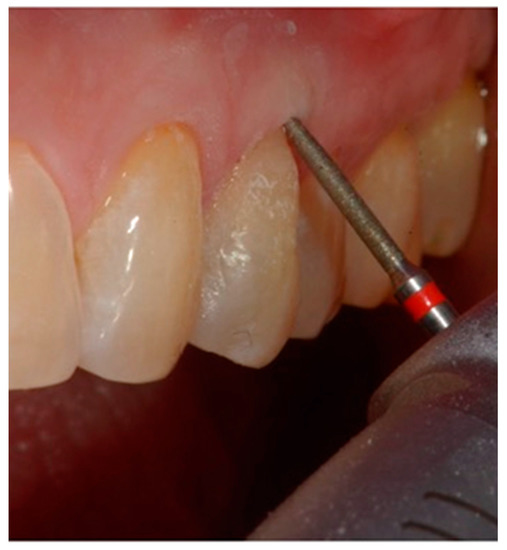

- definition of a small bevel of the enamel (mini-chamfer) in correspondence with the coronal perimeter of the lesion with fine-grained diamond burs to favor the adhesion processes and the mimicry of the restoration and to give sufficient thickness to the most coronal composite (Figure 4).